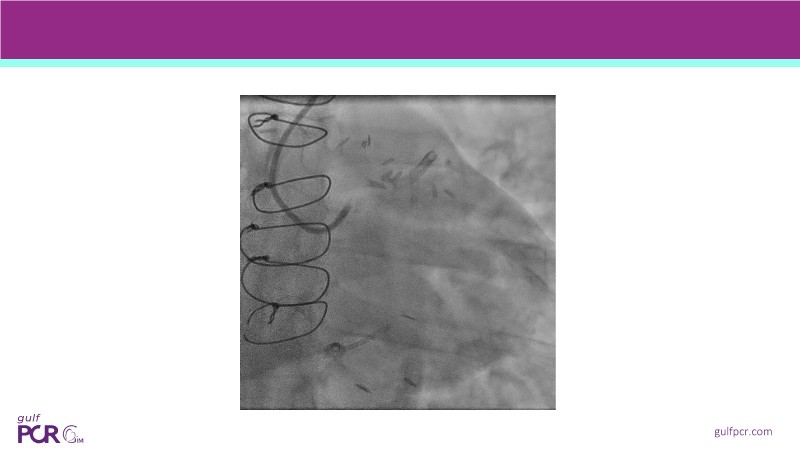

Calcified coronary lesions are a major challenge in PCI. This PCRGulf-GIM 2025 session showcases a complex case with intravascular imaging, highlighting how IVUS 123 guides each step.

From planning the procedure and understanding calcium distribution, to lesion preparation with modern modification tools, and post-PCI assessment to confirm stent expansion and detect complications, this session demonstrates practical, imaging-driven strategies.